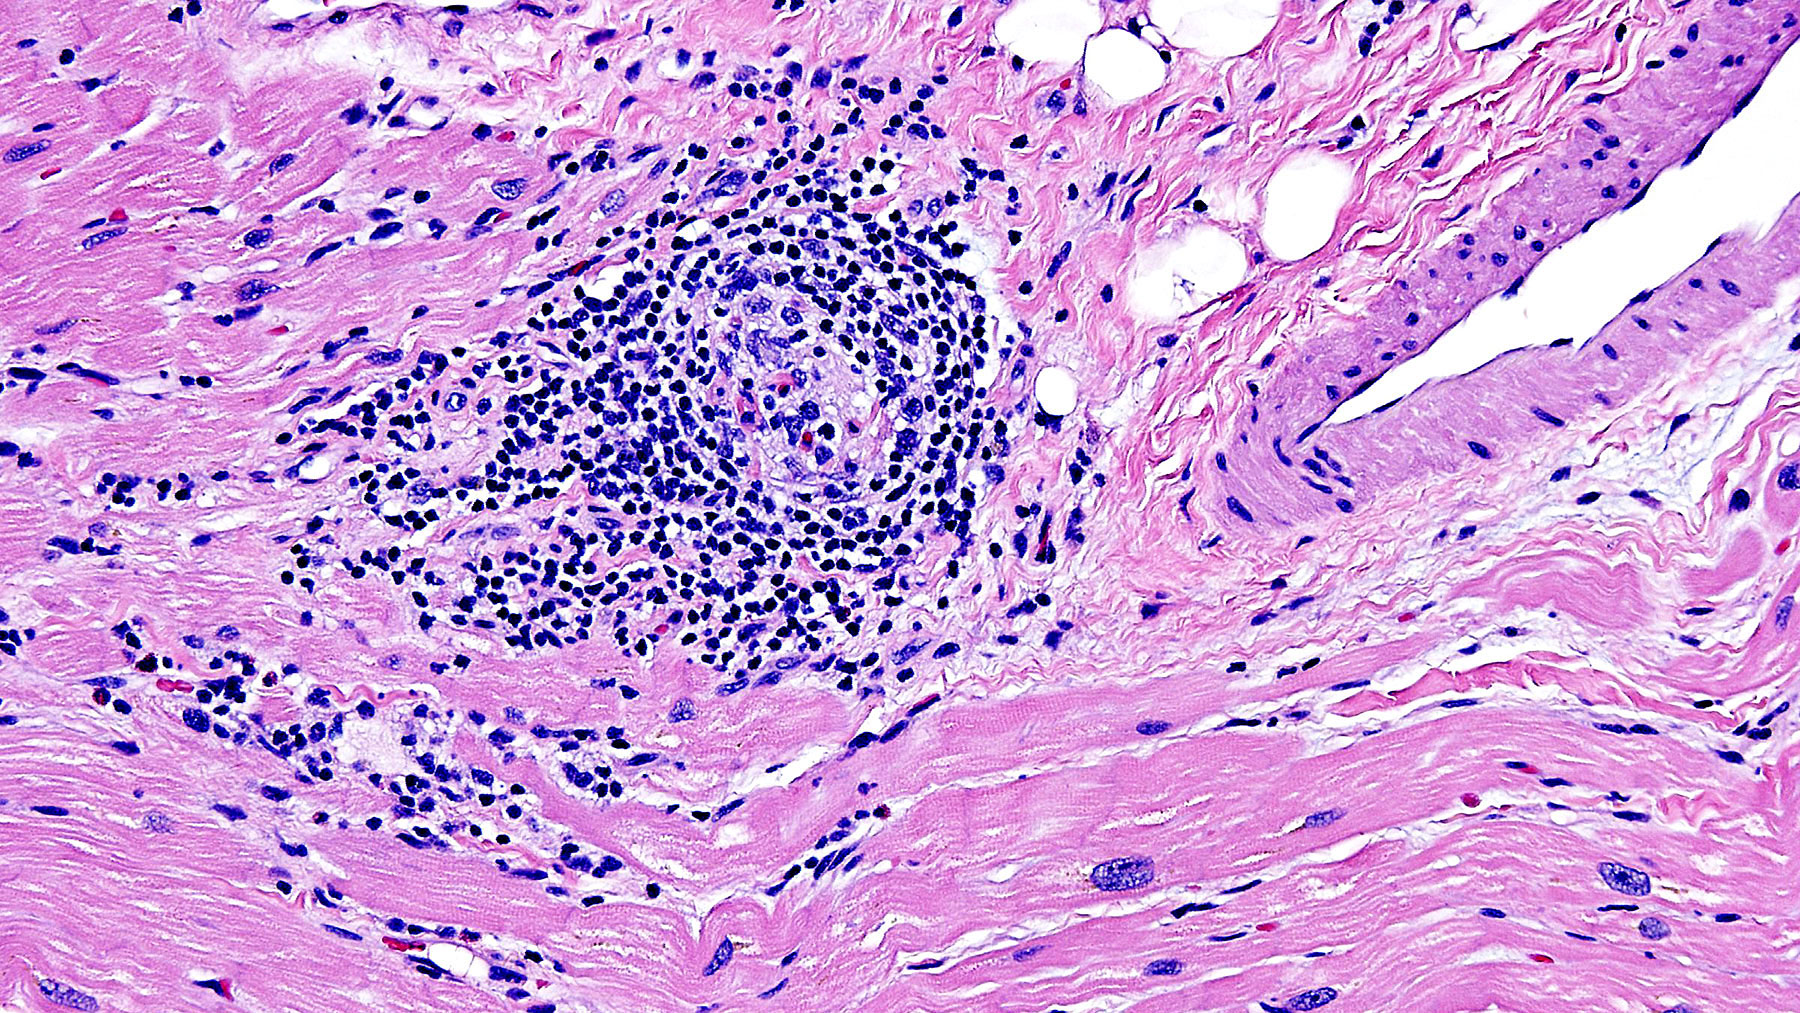

Figure A: H&E staining (10x)

Clinical History: 29 year-old male with history of ulcerative colitis and drug induced lupus developed acute systolic heart failure.

Histology: H&E stains ( Figures A, B, C, and D) show Chronic interstitial myocarditis with mild to moderate infiltration of interstitial spaces with mononuclear cells admixed with scattered eosinophils and diffuse fibrosis.